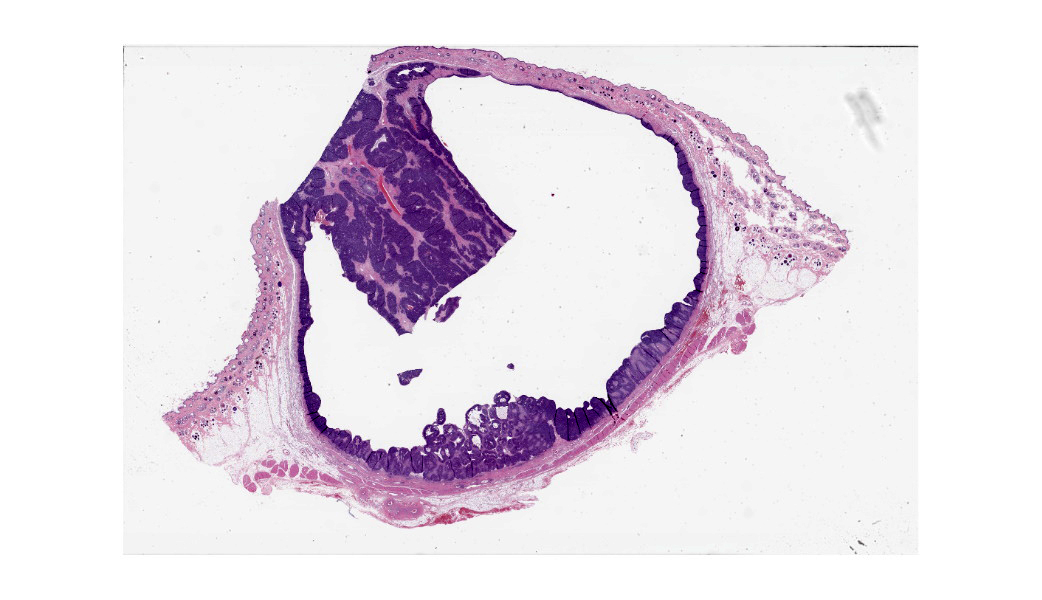

Haired skin: Extending from the dermis deep into the subcutis is an approximately 2 x 2 cm well-demarcated cystic mass lined by neoplastic undifferentiated basaloid epithelial cells. The neoplastic cells are arranged in lobules of dense anastomosing and palisading cords or small tightly packed nests, supported by scant fibrovascular stroma. There are multifocal papillary projections of neoplastic lobules into the lumen of the large cystic cavity. Multifocai lobules have smaller central cyst formation. The neoplastic basaloid cells are cuboidal with scant basophilic cytoplasm and round to oval, hyperchromatic nuclei, with two or more prominent nucleoli. There is minimal anisocytosis and moderate anisokaryosis. There is multifocal abrupt squamous differentiation and necrosis and approximately 5 mitotic figures per high power field. Brown granular pigment, most consistent with melanin, is present throughout the periphery of the mass; multifocal melanomacrophages infiltrate neoplastic lobules. Neoplastic cells extend to within 2 mm of the surgical margin; however, there are multifocal foci suspicious for local invasion.Contributor's Morphologic Diagnoses:

Histologically, basosquamous carcinomas are predominately composed of intradermal to subcutaneous lobules of undifferentiated basal cells with central foci of abrupt squamous differentiation.1 Keratinocytes at the center of neoplastic lobules have mild “nuclear pleomorphism, mitotic activity and dyskeratosis.”1 Unlike other epidermal neoplasms, connection to the overlying epidermis is not a consistent diagnostic feature.4 However, cyst formation and melanization, as seen in this case, are common and can often be appreciated grossly.1,4 Keratinocytes, present in the foci of abrupt and atypical keratinization, that display features of malignancy, along with “the lack differentiation of the follicular isthmus or bulb are features that help differentiate basosquamous carcinomas” from other tumors.4